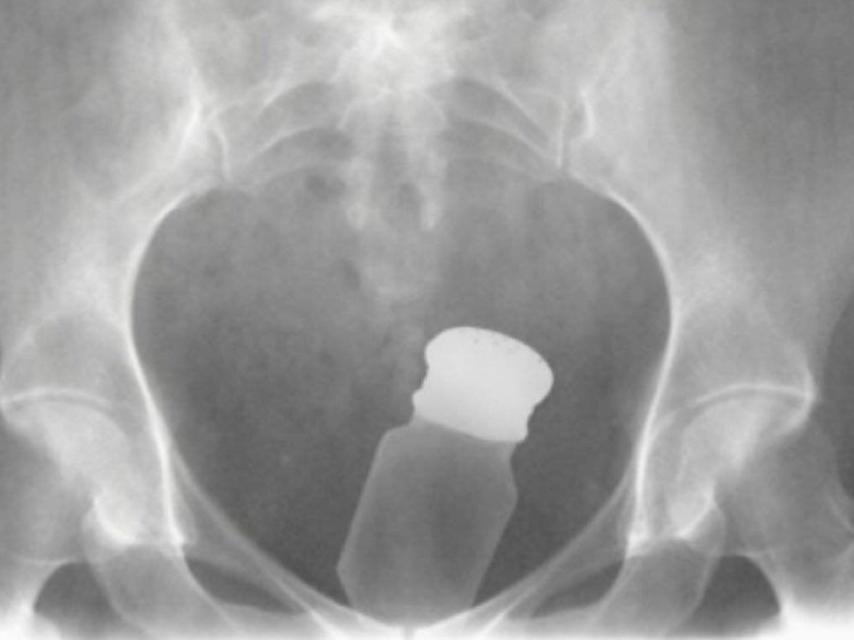

Los presos utilizan el interior de su cuerpo para introducir objetos prohibidos en prisión.

Los presos utilizan el interior de su cuerpo para introducir objetos prohibidos en prisión. EL ESPAÑOL